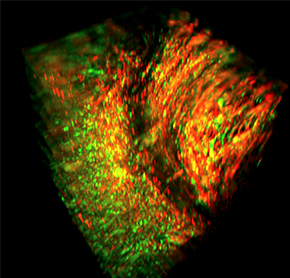

肿瘤检体经过病理染色与医师判读后,确定肿瘤的类型、分级与分期,拟出适合的治疗方案与用药组合。